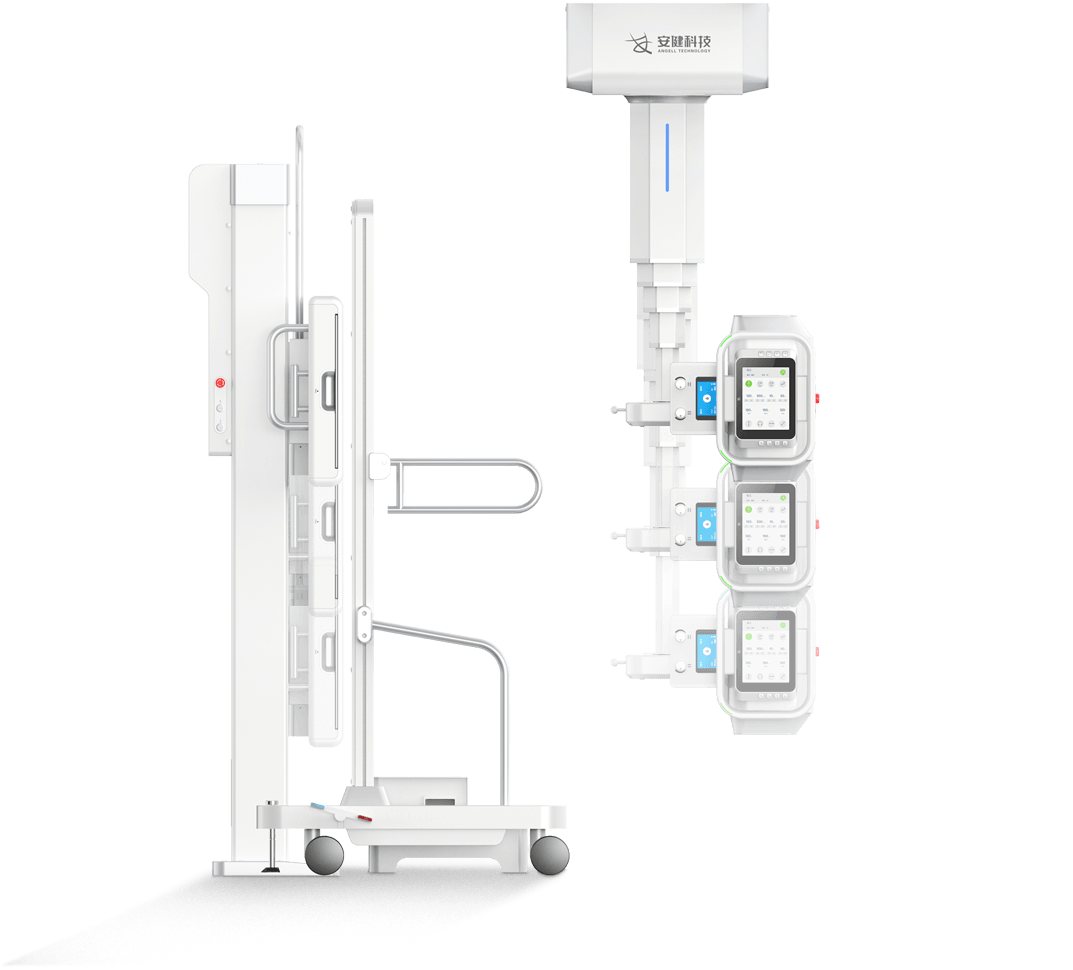

4DК®ЦбБЄ¶ЇФЛ¶ЇПµНі

¶а№¦ДЬРьµхКЅ»ъРµФЛ¶ЇЈ¬И«ЖЅєвОИ¶ЁРФЙијЖЈ¬4DК®ЦбБЄ¶ЇјјКхЈ¬»ъјЬФЛ¶ЇЧФИзЖЅОИЈ¬

ЕдєПµз¶ЇЙэЅµґІј°¶а№¦ДЬБўКЅЙгУ°јЬЈ¬ЗбЛЙВъЧгБЩґІИ«МеО»ЙгУ°РиЗуЎЈ

µз¶ЇЙэЅµґІ

і¬ґуРРіМФЛ¶Ї·¶О§Ј¬Бй»оУ¦¶Ф¶щНЇЎўАПИЛЎўНвЙЛ»јХЯЙППВґІЎЈ

Ед±ёЗ¶ИлКЅёРУ¦ЅвЛшПµНіЈ¬ЗбЛЙµчЅЪґІёЯІўУРР§±ЬГв»јХЯО󴥡Ј

ЗбЛЙёЯР§ІЩЧчБч

¶а№¦ДЬРьµхКЅ»ъРµФЛ¶ЇЈ¬И«ЖЅєвОИ¶ЁРФЙијЖЈ¬4DК®ЦбБЄ¶ЇјјКхЈ¬»ъјЬФЛ¶ЇЧФИзЖЅОИЈ¬

ЕдєПµз¶ЇЙэЅµґІј°¶а№¦ДЬБўКЅЙгУ°јЬЈ¬ЗбЛЙВъЧгБЩґІИ«МеО»ЙгУ°РиЗуЎЈ